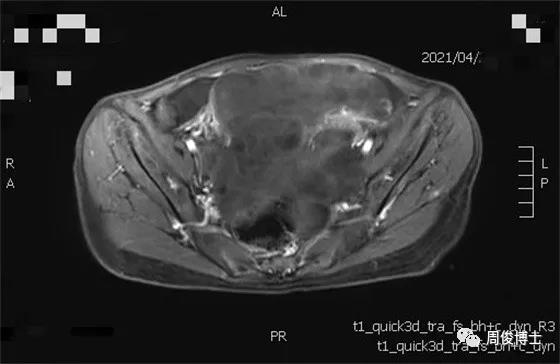

治療七個月后,腫瘤繼續(xù)縮小,腸道通暢,子宮大小恢復(fù)正常,肌肉脂肪豐滿